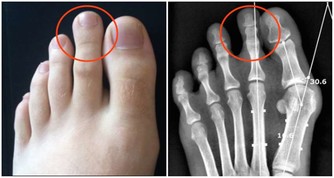

3. 你的腸道裡有寄生蟲

大便中的白色斑點也可能是絛蟲或蟯蟲。雖然如今絛蟲感染並不常見,但依然有可能。如果看到白色或黃色的斑點,可能就是絛蟲,它們通常是扁平的、方形的,大小與米粒相當。有些人可能沒有症狀,但有些人可能出現胃痛或腹瀉。人們通常是因為吃生的或未煮熟的肉而感染絛蟲。絛蟲感染比較好治療,一粒藥丸就足以殺死絛蟲,它會從糞便中排出體外。

大便上出現白點,是什麼原因造成的?

蟯蟲感染更常見,特別是在兒童中。蟯蟲很小,是白色的,大小和訂書針一樣大。

它們通常看起來像白線,所以也被稱為線蟲。

蟯蟲通常生活在腸道的下部,並在肛門周圍的皮膚上產卵,這可能會導致肛門不適和瘙癢。

人們往往是從其他人的大便中被感染蟯蟲卵,

所以去完公共衛生間後徹底洗手,是避免蟯蟲感染的基本常識。

治療蟯蟲的藥物一般分兩次服用,而且家中的每個人都需要治療,以確保他們沒有感染。

另外,要定期清洗衣物和床上用品,以避免再次感染,經常洗手、指甲別留太長,也是重要的防護措施。